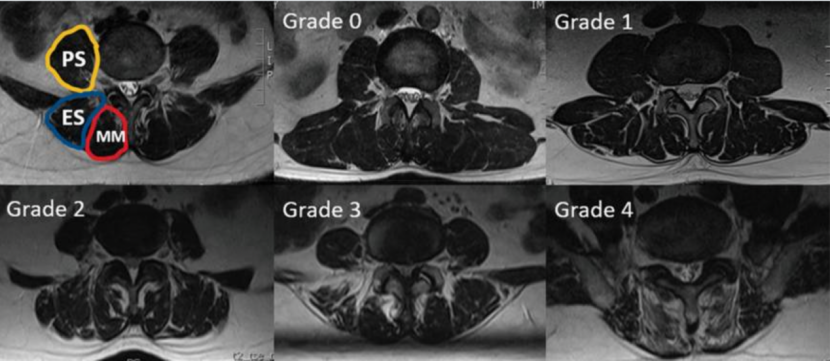

为什么会有单关节器械关节镜下肩袖修复:单排 vs 双排缝合,如何选择?_https://www.jmylbn.com_新闻资讯_第5张

图 4:Goutallier 分级。0 级:无肌内脂肪;1 级:可见少量脂肪条纹;2 级:可见脂肪,但少于肌肉组织;3 级:脂肪量与肌肉量相等;4 级:脂肪量多于肌肉组织。图源:文献 2